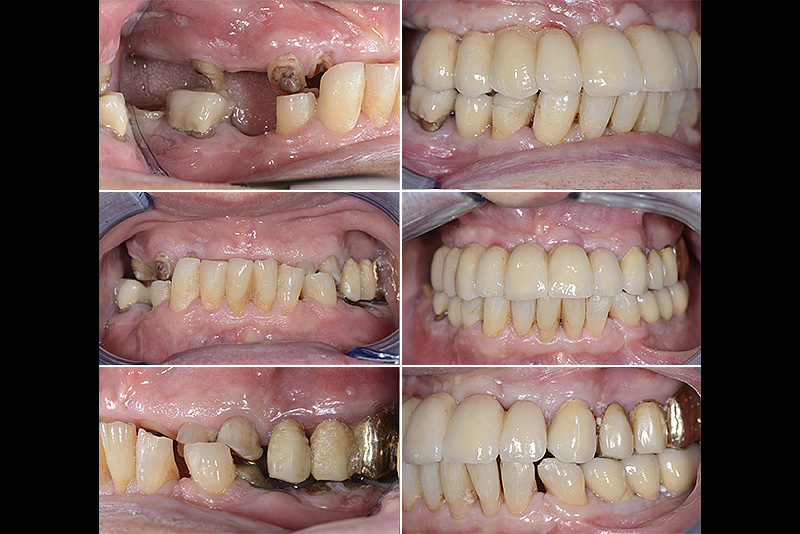

PREMESSA: in seguito all’estrazione dell’incisivo laterale superiore di destra, resasi necessaria per cause batteriche, si decide di affrontare il caso con il posizionamento di un impianto in sostituzione dell’elemento mancante dopo guarigione del sito infetto. Con tecniche rigenerative sia dei tessuti ossei mancanti a causa dell’infezione pregressa, sia dei tessuti gengivali che appaiono inizialmente troppo spostati in alto, si ripristina una corretta morfologia delle parabole (contorni) gengivali e delle papille interdentali (triangoli di gengiva tra due denti vicini).

Vengono utilizzati 2 tipi di provvisori: il primo, cementato ai denti vicini, viene utilizzato dal momento dell’estrazione del dente fino ad impianto osteointegrato (circa 6 mesi); il secondo, avvitato direttamente all’impianto, ha una funzione di prova estetica ma soprattutto di guida per la maturazione dei tessuti gengivali peri-implantari portandoli verso la maturazione completa prima di posizionare la corona finale in disilicato di litio.